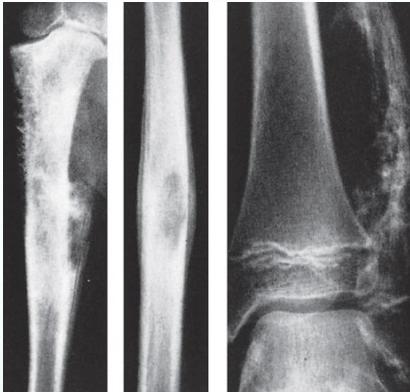

Radiological Features

- X-ray:

- Diaphyseal

- Bone destruction

- New bone formation:

- Along the bone

- “Onion-peel” layers

- ? “Sun-ray”

- ? Codman’s triangle

- Secondaries – in skeleton

Source: Apley’s System of Orthop. And Fractures